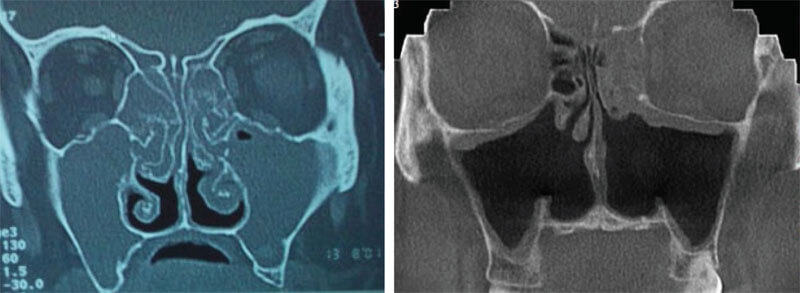

Хирургия восстановления носового дыхания и придаточных пазух носа

Восстановление носового дыхания (эндоскопическим трансназальным способом).

Удаление полипов, инородных тел, носа и придаточных пазух, трансназальным эндоскопическим способом.

Устранение одонтогенных гайморитов и осложнений после синус лифтинга.